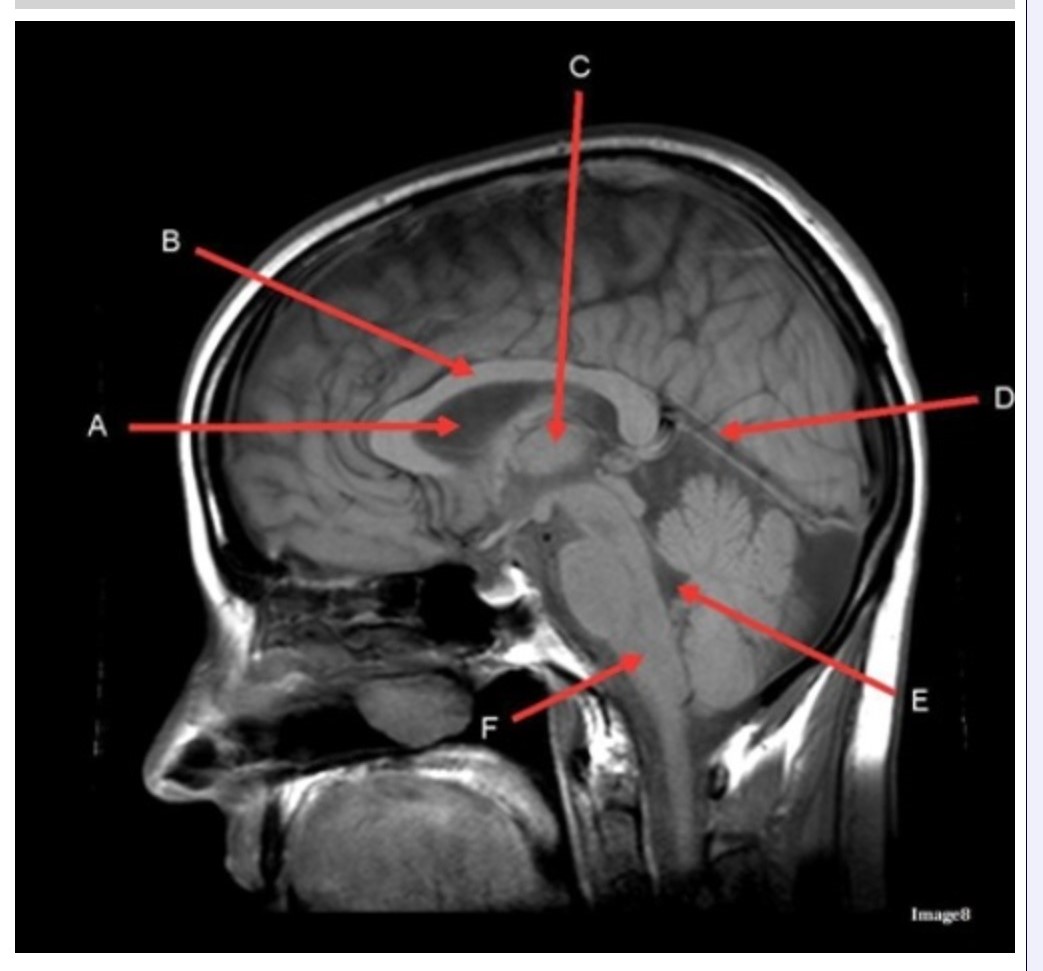

Letter C in Image 8 is pointing to:

A. Tentorium

B. Corpus callosum

C. Thalamus

D. Fourth ventricle

E. Medulla oblongata

Letter F in Image 8 is pointing to:

A. Tentorium

B. Cerebellum

C. Thalamus

D. Fourth ventricle

E. Medulla oblongata

Letter A in Image 8 is pointing to:

A. Tentorium

B. Corpus callosum

C. Hypothalamus

D. Fourth ventricle

E. Lateral Ventricle

Letter E in Image 8 is pointing to:

A. Tentorium

B. Cerebellum

C. Thalamus

D. Fourth ventricle

E. Medulla oblongata

Letter B in Image 8 is pointing to:

A. Tentorium

B. Corpus callosum

C. Hypothalamus

D. Fourth ventricle

E. Medulla oblongata

Letter D in Image 8 is pointing to:

A. Tentorium

B. Cerebellum

C. Thalamus

D. Fourth ventricle

E. Medulla oblongata

Image 8 is an example of a _______ weighted sequence acquired in the _______ scan plane.

A. T1; Axial

B. T1; Sagittal

C. T2; Axial

D. T2; Sagittal